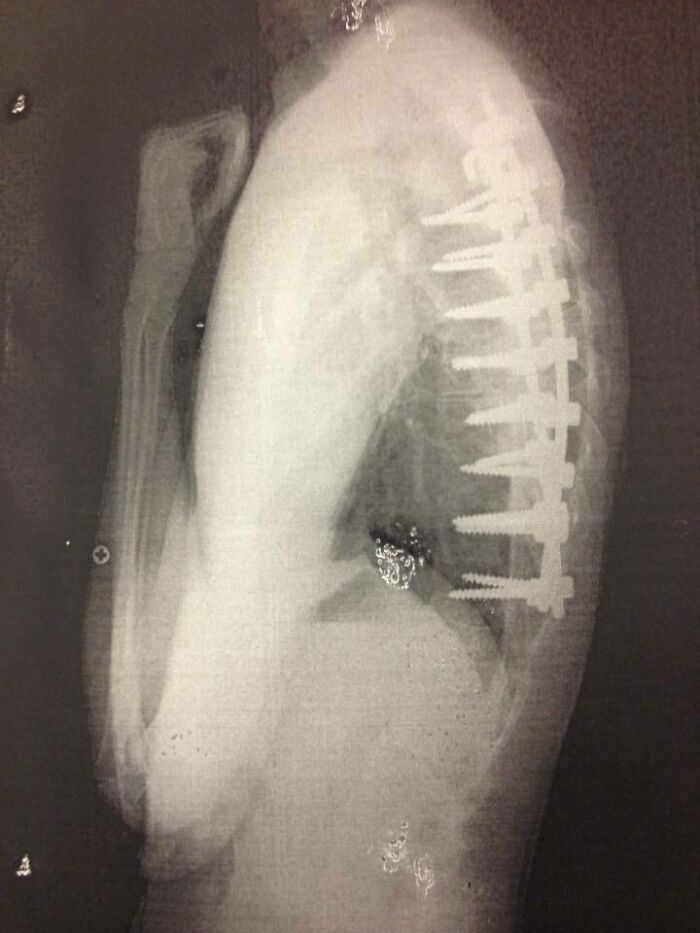

#31 In My Head, The Screws From My Spinal Fusion Surgery Looked A Lot Smaller

Image credits: reddit.com